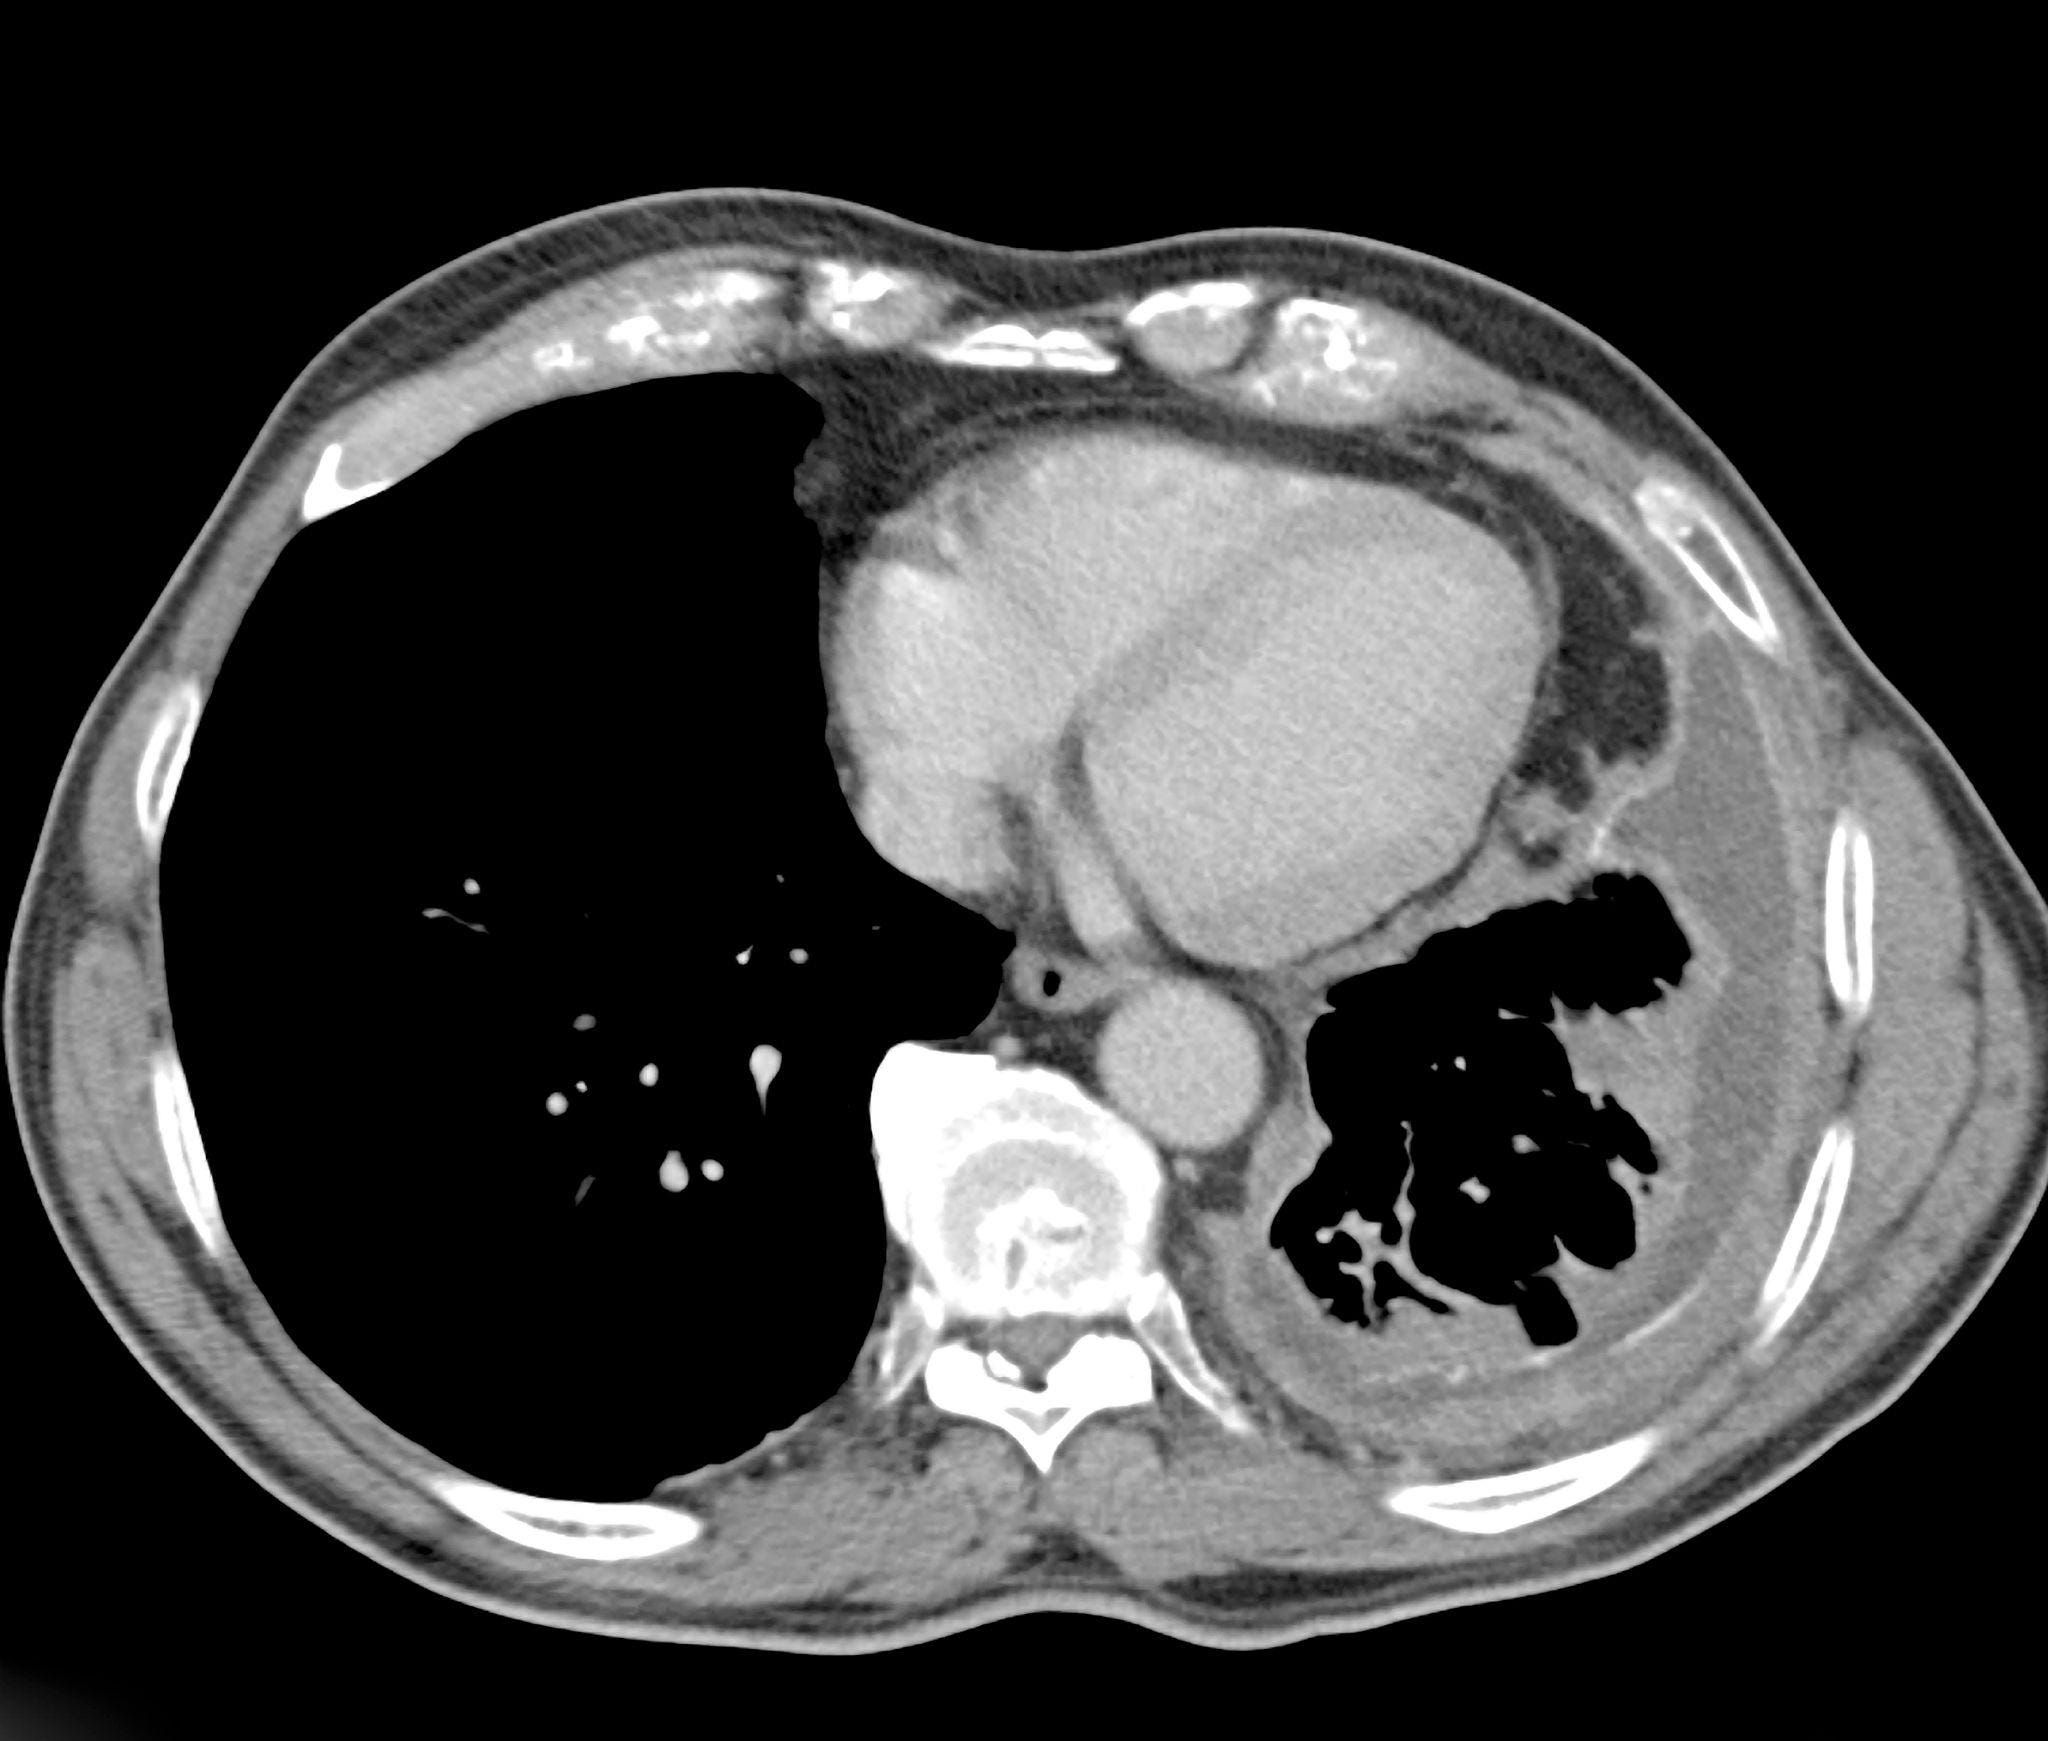

Bard PowerPort

The Bard PowerPort is an implanted catheter device used to deliver medications directly into the bloodstream, often for chemotherapy or long-term treatment. Lawsuits allege that the device can fracture or migrate, causing serious internal injuries, blood clots, infections, and the need for surgical removal. Manufactured by C. R. Bard, the product is the subject of a rapidly growing MDL. Plaintiffs claim the device was defectively designed and that safer alternatives were available. The litigation is currently in the coordinated discovery phase, with thousands of cases pending and expectations for future bellwether trials.